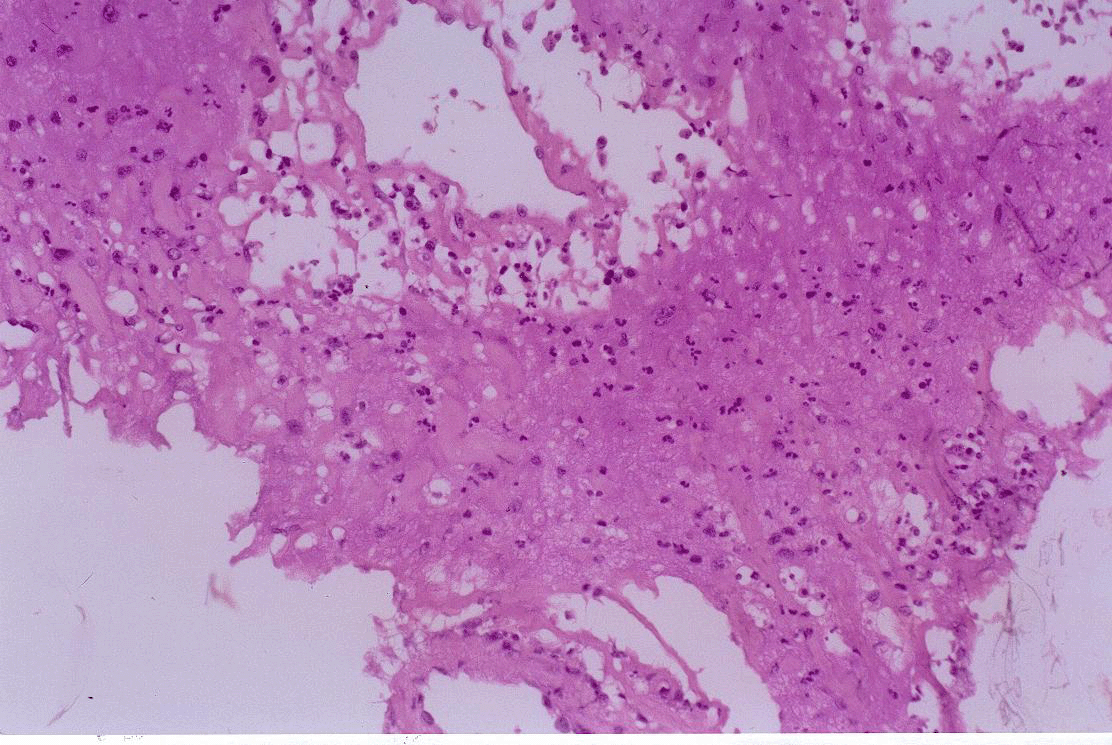

Elle ?tait en bon ?tat g?n?ral, malgr? un f?bricule ? 37,8 C? et des polyarthralgies. Il n'y avait pas d'ad?nopathie satellite ni d'oed?me des membres inf?rieurs. L'?cho-doppler veineux du r?seau vulvo-p?rin?al ne montrait pas de thrombose. La NFS r?v?lait une polynucl?ose neutrophile ? 20?700 par ml. La CRP ?tait normale (< 5 mg/l). Vingt-quatre heures plus tard, on constatait la disparition de l'induration de la grande l?vre et l'apparition d'une volumineuse formation fluctuante sous-cutan?e. L'oed?me et la douleur persistaient. Le pr?l?vement biopsique a permis le drainage spontan? d'un liquide purulent, riche en polynucl?aires neutrophiles et st?rile microbiologiquement, et sans lamelle de k?ratine. L'examen histologique montrait un oed?me et une infiltration de l'hypoderme par des polynucl?aires neutrophiles sans vascularite ni image granulomateuse ou lamelles de k?ratine ni de cellules s?bac?es, la coloration PAS ?tait n?gative. Le drainage chirurgical ?tait inefficace (r?cidive apr?s 7 jours). L'ensemble du tableau clinique et biologique r?gressait apr?s 10 jours de traitement par Prednisone (0,4 mg/kg/jour).